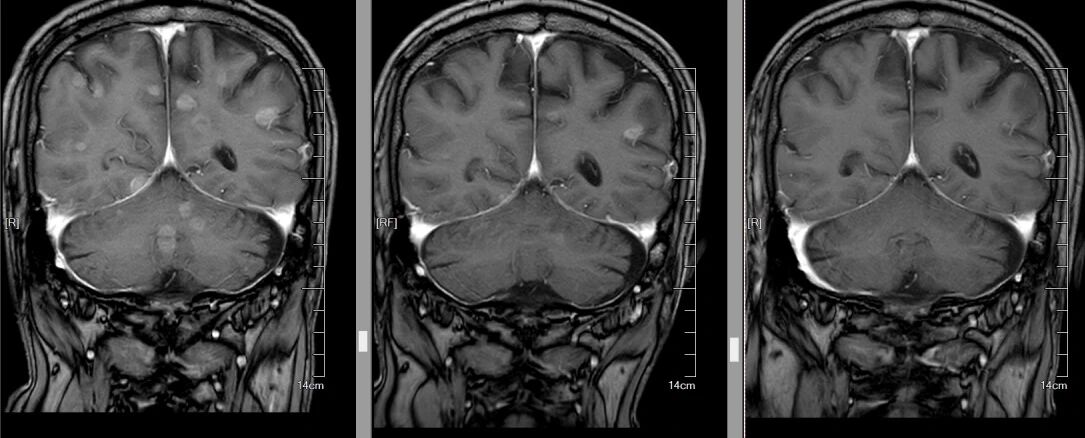

△从左至右,颅内肿瘤逐渐减少

当肿瘤科将最新的胸部CT和头颅MRI图像调出来时,结果让人振奋:双肺原本密密麻麻的粟粒样转移结节,大多缩小至模糊不清,肺部原发灶也小了很多;双侧胸膜增厚明显变薄,原本被肿瘤侵犯的纵隔淋巴结也显著缩小;最令人惊喜的是头颅MRI,之前的十余处脑转移灶消失,近乎达到了肿瘤治疗中极具含金量的完全缓解(CR)标准!